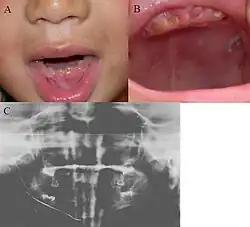

Oral photographs from an individual with Dentinogenesis imperfecta

People with this condition have abnormal enamel, short and narrow roots, and can lack nerves. This condition can cause teeth to be discolored (most often a blue-gray or yellow-brown color) and translucent, giving teeth an opalescent sheen.[2][3][8][5][9] Teeth are also less mineralized than normal, making them prone to rapid wear, breakage, and loss.[2][3][4][5][8] These problems can affect primary (baby) teeth alone, or both baby teeth and permanent (adult) teeth, with the primary teeth usually more severely affected.[5][8]

• Discolored teeth - teeth may be amber, brown, blue or opalescent

• Bulbous shape to the tooth crown due to cervical constriction

• Tooth wear/Non-carious tooth surface loss (NCTSL) - due to the poorly mineralized dentin, the enamel of the tooth is unsupported and subsequently shears or chips off as it is subjected to occlusal (biting) forces. This exposes the underlying less mineralized dentin which is less resistant to wear. Therefore, features of abrasion and attrition may become apparent.

The primary (baby) teeth are usually more severely affected than permanent (adult) teeth.[3][5][8]

Radiographic presentation

Radiographic features include:

• Bulbous shape of tooth crown with pronounced cervical constriction

• Small pulp, or total pulp obliteration

• Small or obliterated root canal

• Presence of pulp stones

• Narrow and small roots

• Periapical radiolucency without any evidence of clinical pathology such as tooth decay (dental caries)[2][3][5][14]